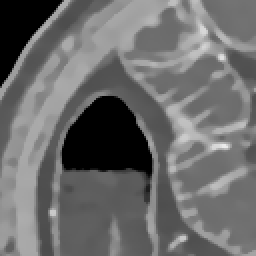

Elimination of noise in ultra low dose CT data

after smoothing